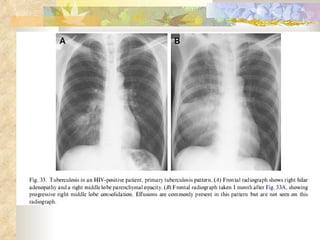

A posteroanterior (A) and lateral (B) chest radiograph of a child with hilar adenopathy caused by Mycobacterium tuberculosis.

A posteroanterior (A)and lateral (B) chest radiograph of a child with hilar adenopathy caused by Mycobacterium tuberculosis.